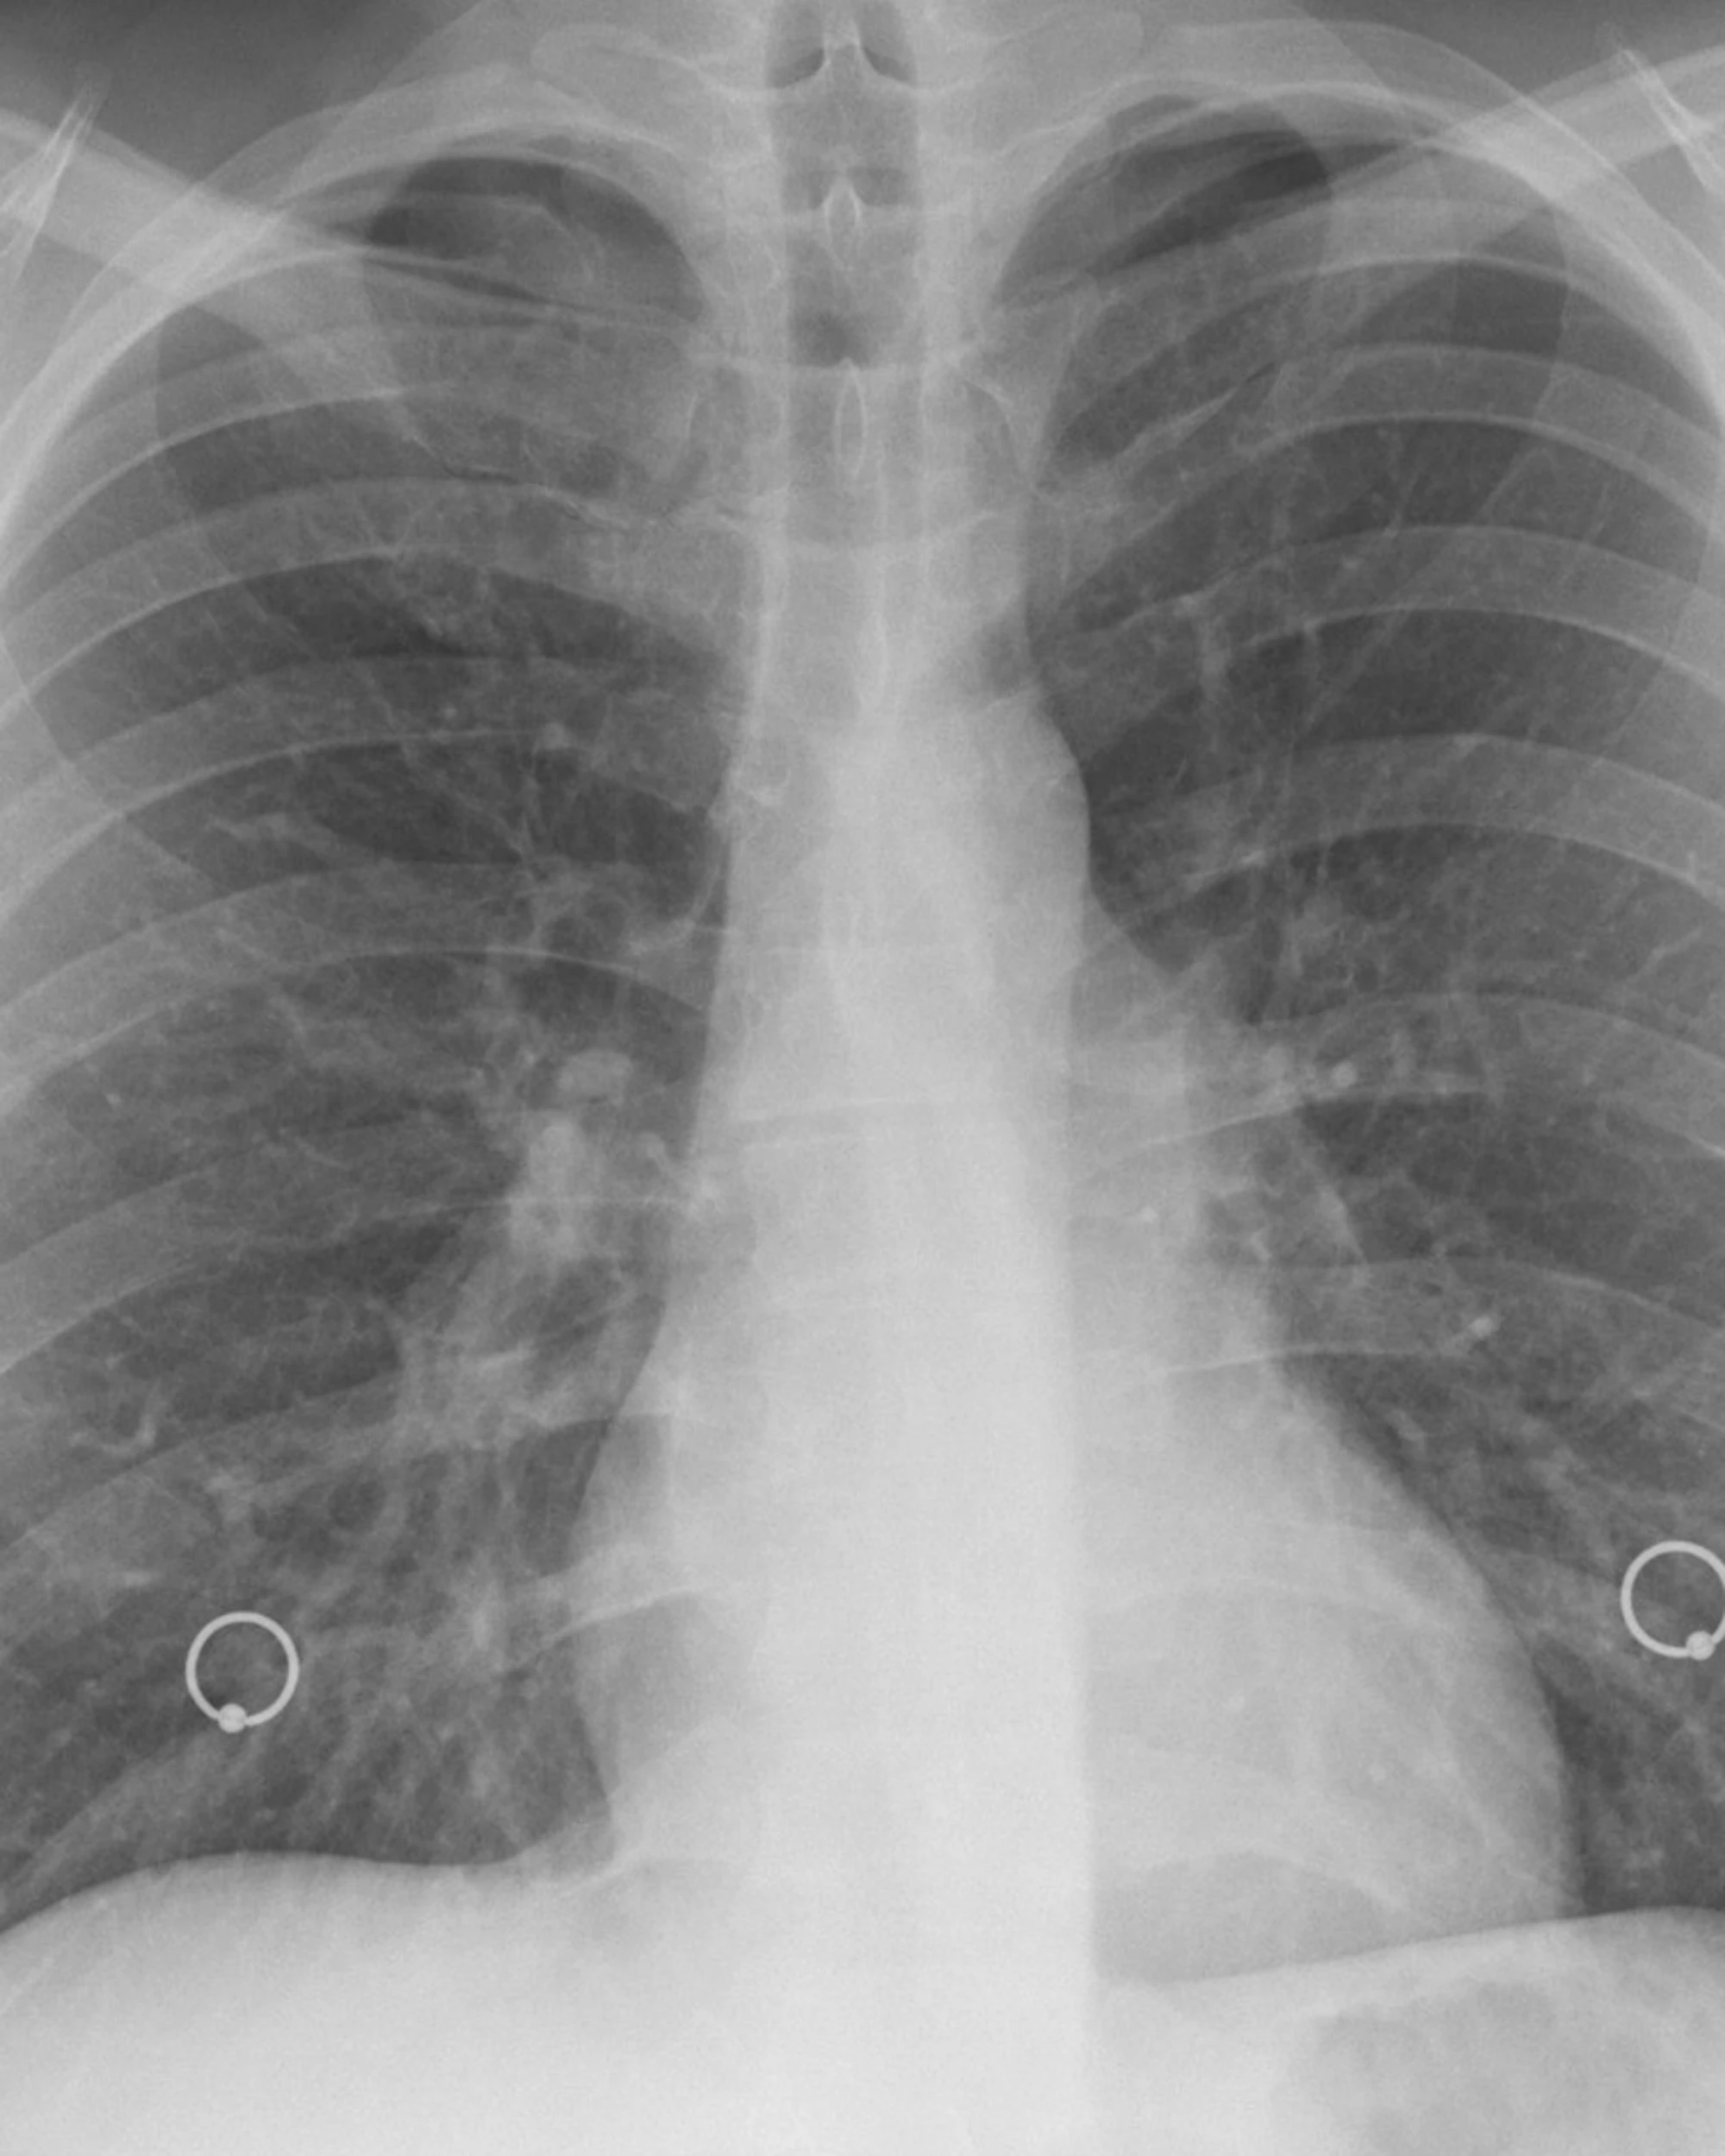

Un importante passo avanti nella cura del tumore del polmone avanzato arriva da uno studio internazionale pubblicato di recente sulla prestigiosa rivista scientifica JAMA Oncology. La ricerca, frutto di una collaborazione tra centri di eccellenza in Italia e Stati Uniti, che ha coinvolto con il coordinamento dell'IFO-Istituto Nazionale Tumori Regina Elena (IRE), il Dana-Farber Cancer Institute di Boston, il Memorial Sloan Kettering Cancer Center di New York, propone un approccio terapeutico innovativo per i pazienti affetti da carcinoma polmonare non a piccole cellule (NSCLC) in stadio III avanzato e non operabili

Il carcinoma polmonare in stadio III borderline resecabile o non resecabile rappresenta una delle sfide più difficili in oncologia, con opzioni di trattamento spesso poco efficaci. I risultati di questo studio offrono nuove speranze, indicando che un'attenta selezione dei pazienti e l'impiego strategico dell'immunoterapia prima della chirurgia possono cambiare la storia clinica della malattia. La chemioterapia insieme alla radioterapia sono lo standard terapeutico per il tumore polmonare non a piccole cellule, non operabile, mentre la chemio-immunoterapia neoadiuvante offre un'alternativa emergente per i tumori in stadio III resecabili ma borderline.

Lo studio ha dimostrato che l'associazione tra chemioterapia e immunoterapia - somministrata prima dell'intervento chirurgico - può migliorare significativamente l'efficacia del trattamento anche nei casi più complessi e con prognosi sfavorevole. In particolare, il trattamento combinato con farmaci che bloccano le proteine PD-1 o PD-L1, coinvolte nel "camuffamento" del tumore rispetto al sistema immunitario, ha permesso di rendere operabili 3 pazienti su 4, con una risposta completa alla terapia in quasi un terzo dei casi.